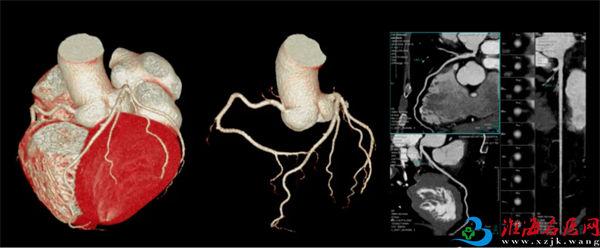

1 全身CTA检查

全身CTA包括冠脉CTA、头颈CTA、肺动脉CTA、下肢动脉CTA及胸腹主动脉CTA等。尤其在西门子Drive双源平台,可以做到个性化冠脉CTA。针对高心率、心率不齐、房颤等患者,可以根据检查者本身的实际情况和检查目的选择更加适合的扫描方案。前瞻序列、前瞻大螺距、回顾螺旋扫描方式充分满足不同患者情况,做到精准检查的同时合理优化辐射剂量。